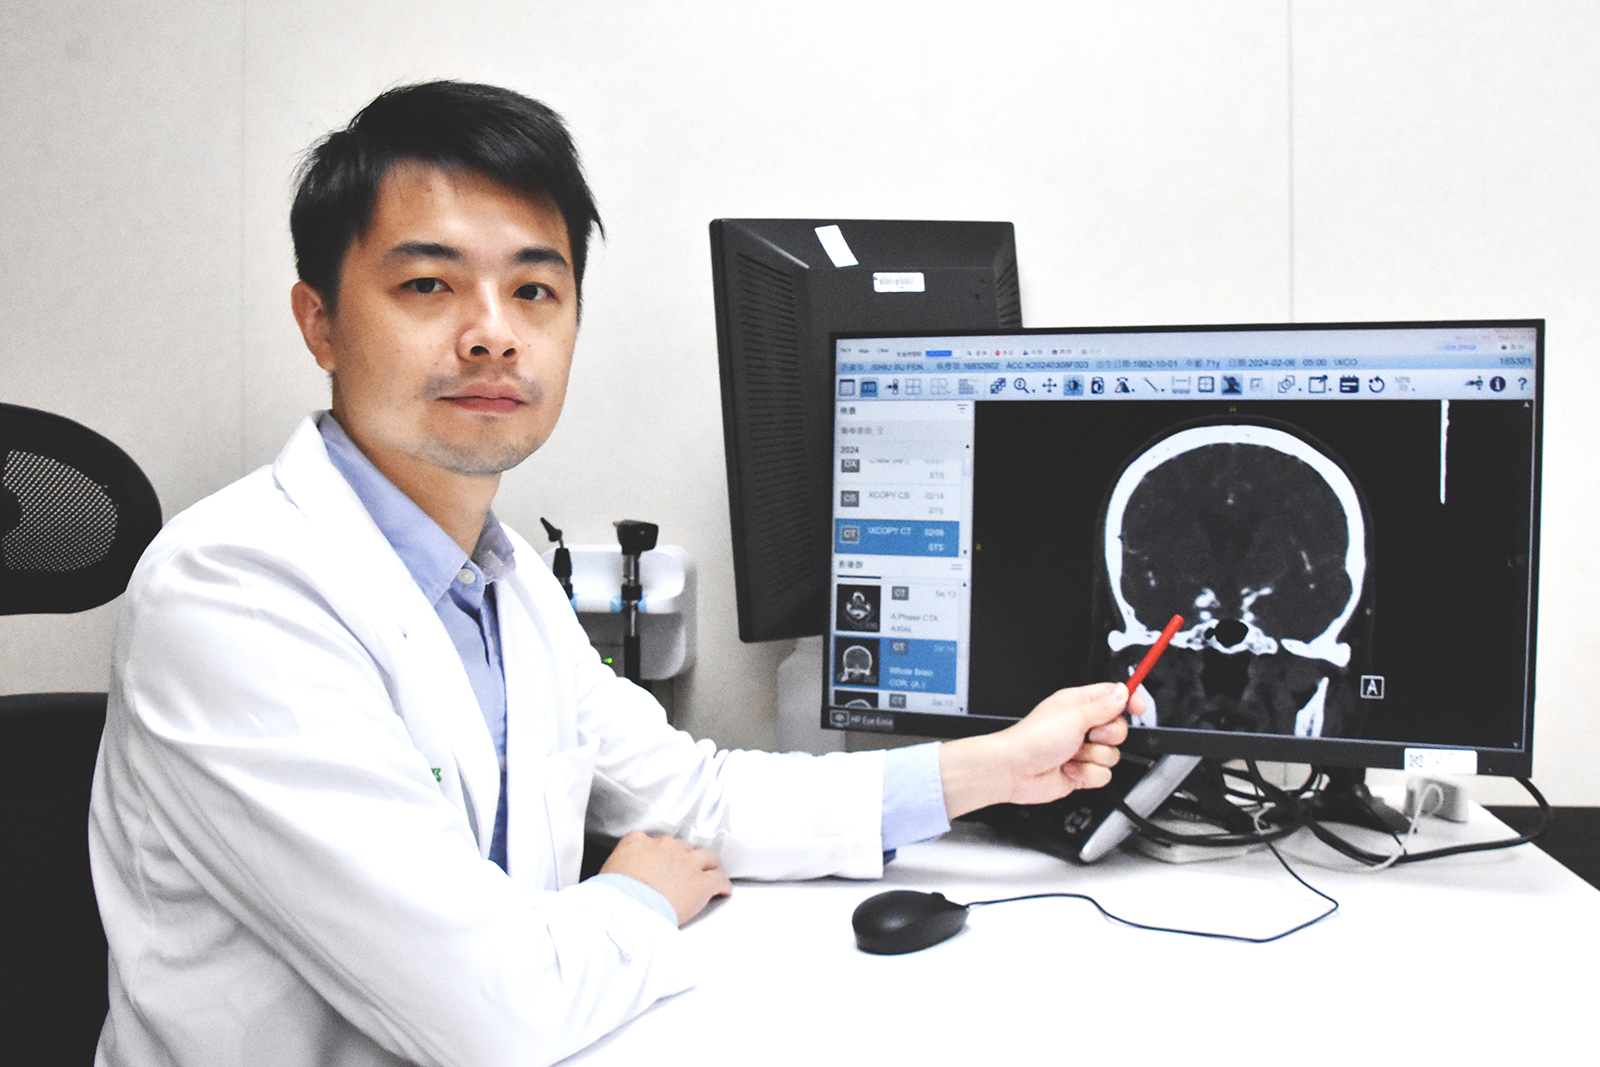

(觀傳媒彰化新聞)【記者陳雅芳/彰化報導】80歲曾姓婆婆頭暈目眩雙眼複視、畏光,經眼科診所治療後不僅未改善,甚至呈現「睜隻眼、閉隻眼」狀態,經轉診至彰基醫學中心神經外科門診,發現長達8mm右側顱內後交通動脈瘤,造成動眼神經壓迫,經開顱動脈瘤夾除手術後,右眼皮可以張開,右眼轉動也漸漸恢復正常,畏光與複視重影症狀也獲改善。

▲郭明錡醫師表示,曾姓婆婆經檢查發現長達8mm右側顱內後交通動脈瘤,造成動右眼神經壓迫。

(彰基醫院提供)

經眼科轉診至神經外科門診,在門診時發現婆婆右眼皮下垂無力,右眼球只能朝外轉動,不能朝內轉也無法向上轉動,立即將病患安排緊急電腦斷層血管攝影,發現竟是長達8mm的右側顱內後交通動脈瘤,造成動眼神經壓迫,經安排至手術室進行開顱動脈瘤夾除手術,術後住院7天即出院返家休養。